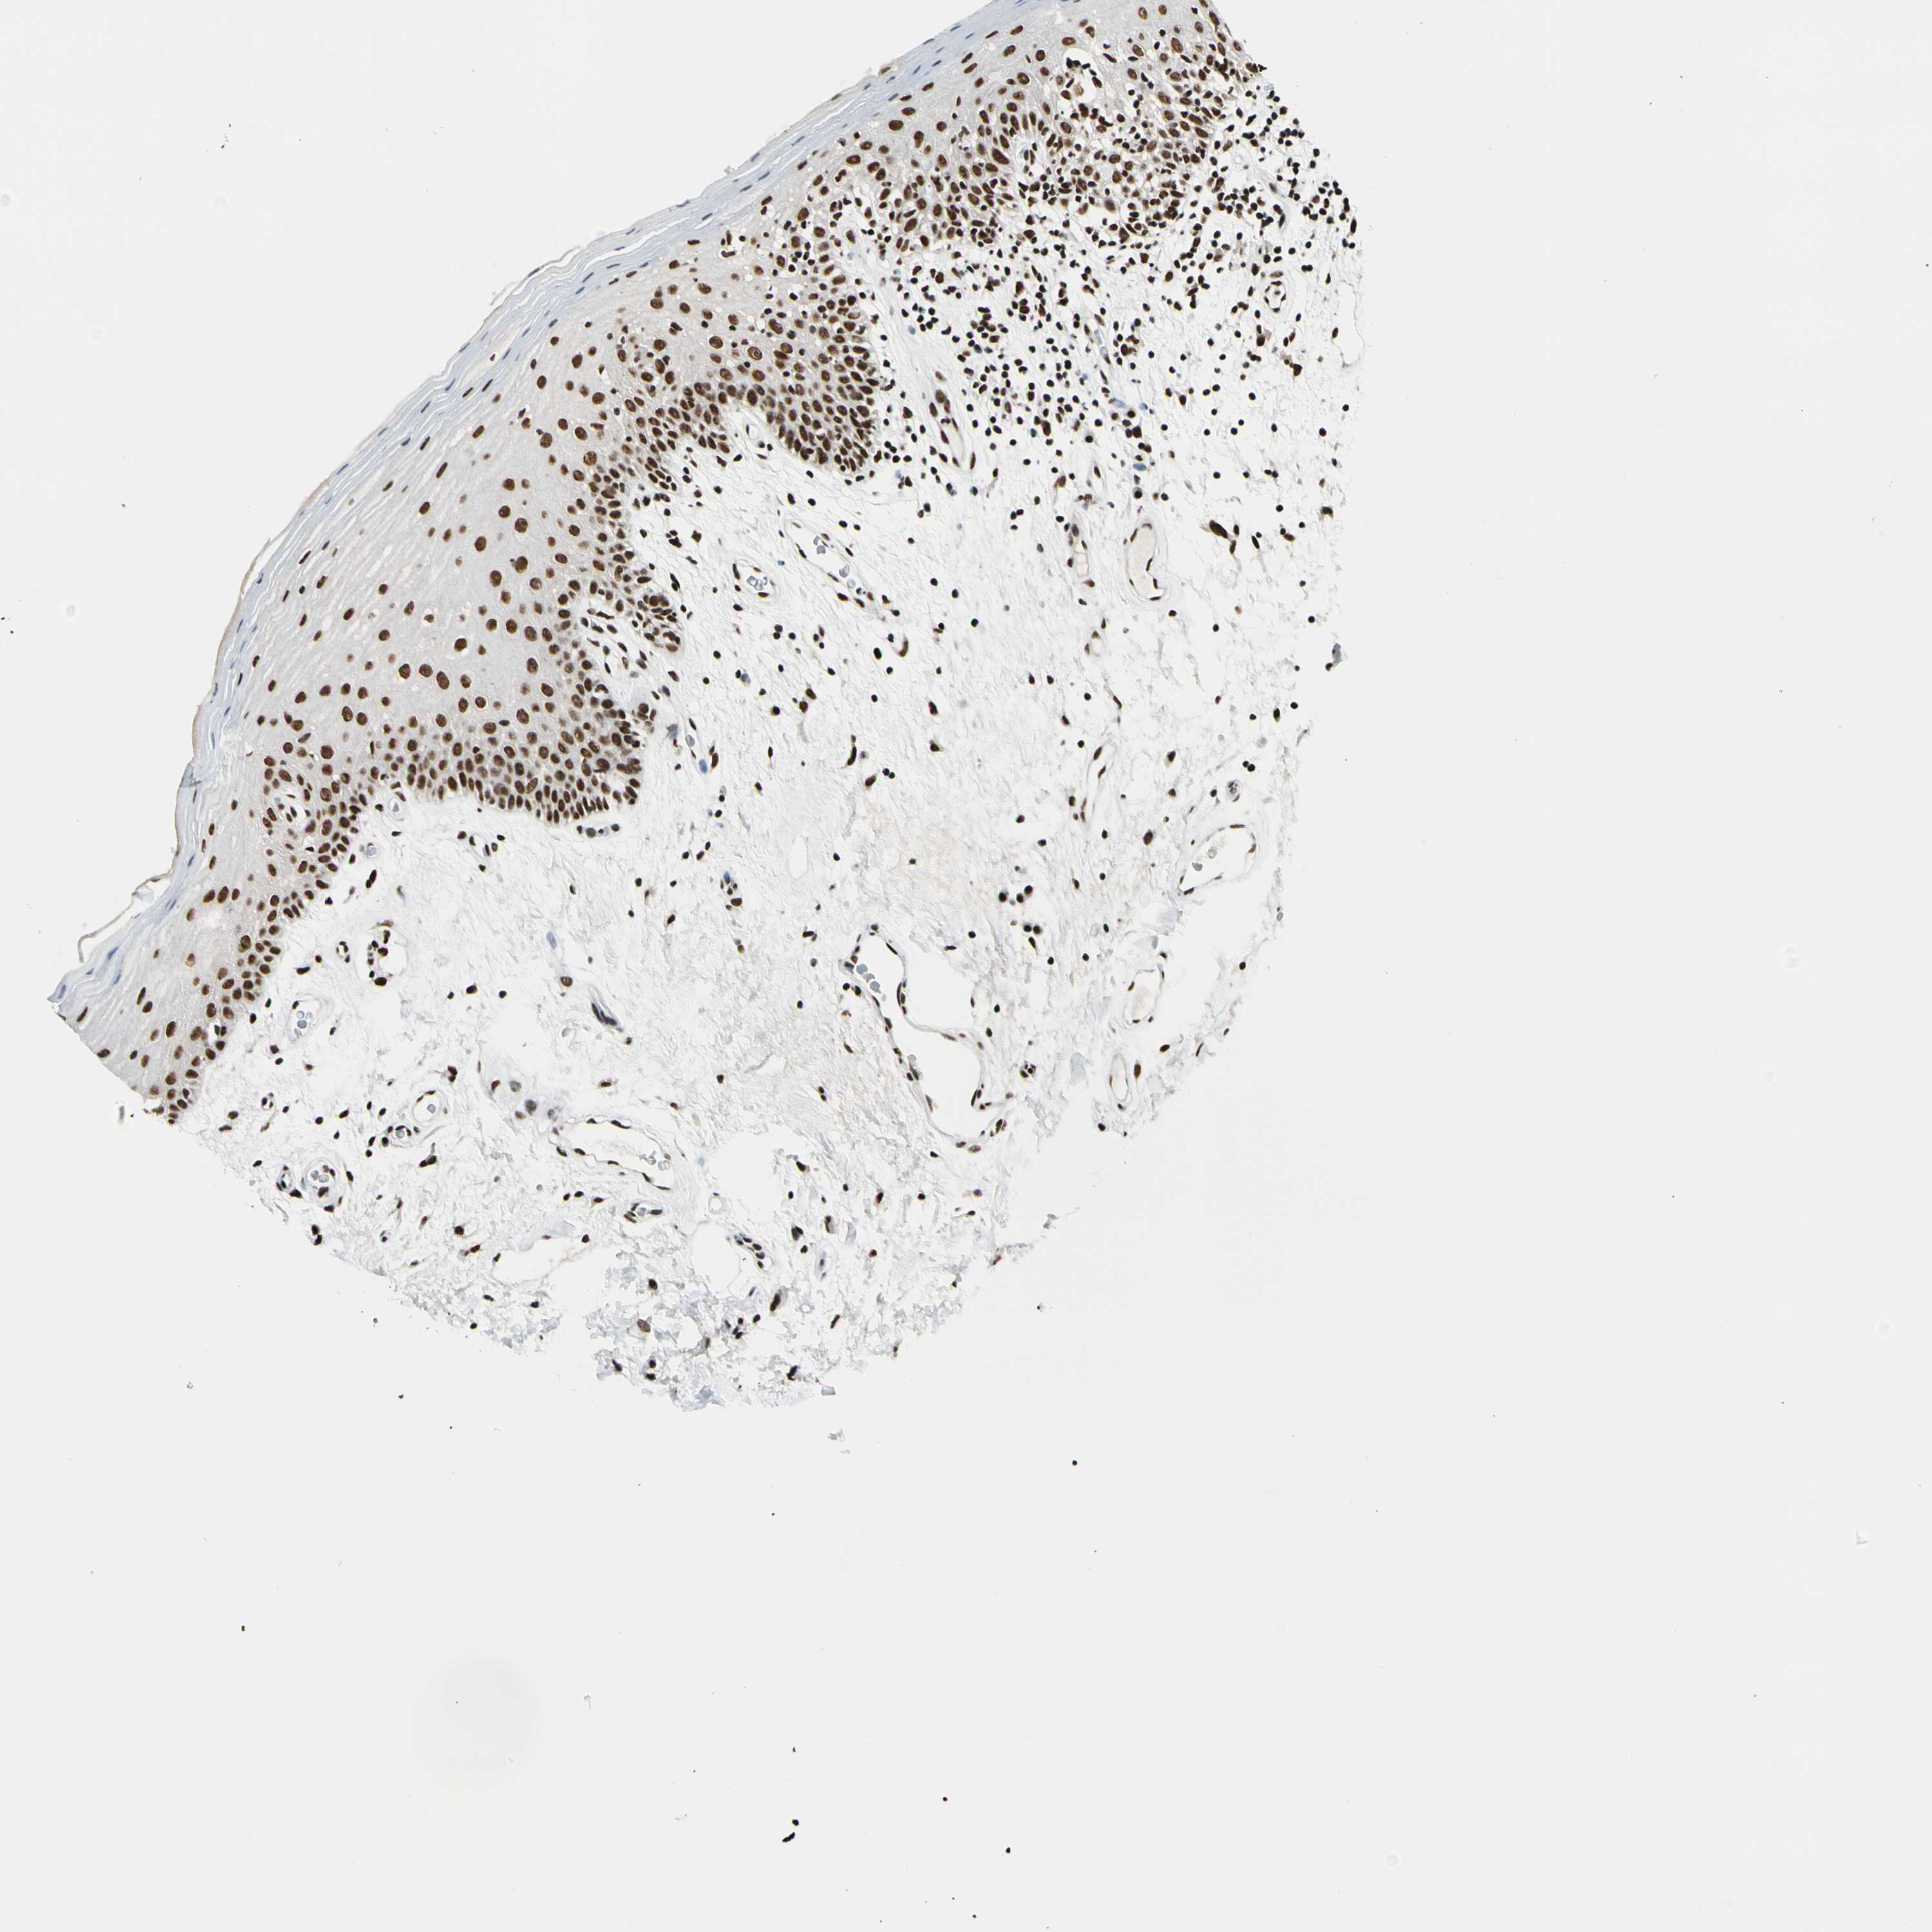

TISSUE PRIMARY DATA ORAL MUCOSA Show tissue menu

ORAL MUCOSA - Antibody stainingi

Antibody staining in the annotated cell types in the current human tissue is reported as not detected, low, medium, or high, based on conventional immunohistochemistry profiling in selected tissues. This score is based on the combination of the staining intensity and fraction of stained cells.

Each image is clickable and will lead to virtual microscopy that enables deeper exploration of all samples and also displays staining intensity scores, fraction scores and subcellular localization as well as patient and tissue information for each sample.

Antibody HPA007856Antibody HPA048513

Squamous epithelial cells HighHigh